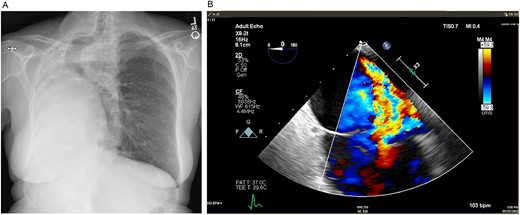

Turning attention to the tricuspid valve, pledgeted, transannular 2–0 Ethibond sutures were placed circumferentially in everting fashion (atrial side to ventricular side), taking care to place superficial sutures buttressed with the septal leaflet near the atrioventricular node. The annular sutures were brought through the sewing ring of a 33 mm St. Jude Medical Epic bioprosthetic valve that was seated on the annulus, and the annular sutures were secured and cut using the CoreKnot device (LSI Solutions; Minneapolis, MN). Leaflet motion and competence of the valve were confirmed with saline. The right atriotomy was then closed in two layers of 4–0 Prolene. After delivering a dose of terminal warm blood cardioplegia, the aortic cross-clamp was released on low flow CPB. The heart was reperfused, and normal sinus rhythm resumed. With normal biventricular function, the patient was weaned and decannulated of CPB. After achieving hemostasis, the right posterolateral thoracotomy incision was closed. The patient was then taken to the cardiovascular intensive care unit in stable condition. On 8-month follow-up, mean gradient across the tricuspid valve prosthesis was 5 mmHg, RV size and function had returned to normal and the patient had normal exercise tolerance and was feeling well (Fig. 3).

(A) Postoperative posteroanterior view chest X-ray. (B) Postoperative transesophageal echocardiogram with doppler showing a well-seated bioprosthetic valve in the tricuspid position with a mean gradient of 4 mmHg and no measurable insufficiency.